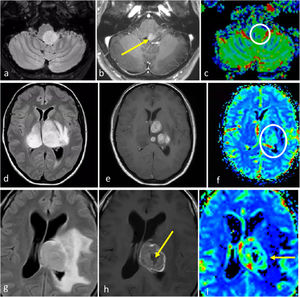

Tres presentaciones típicas diferentes del glioblastoma IDH-wildtype en pacientes de entre 60 y 70 años. a-c) características paradigmáticas en imágenes axiales T1w poscontraste de tres pacientes diferentes, con márgenes irregulares, realce en anillo y necrosis extensa. d-f) FLAIR axial, T1w poscontraste y mapas de color del CBV de DSC-PWI. Extensa lesión infiltrante temporal izquierda en FLAIR (d) con realce nodular sólido asociado y sin necrosis (flecha en d), pero con CBV claramente elevado (círculo en f). g-i) FLAIR axial, T1w poscontraste y mapas de color de CBV de DSC-PWI. Lesión infiltrante temporal izquierda en FLAIR focal (g) con realce mínimo y ausencia de necrosis (flecha en h), pero con CBV claramente elevado (círculo en i).

CBV: volumen sanguíneo cerebral; DSC-PWI: imagen de perfusión dinámica; IDH: gen isocitrato deshidrogenasa.

En ciertos casos, el glioblastoma puede manifestarse sin necrosis clara y presentar predominantemente un patrón infiltrante. Estos tumores se caracterizan por mayores componentes no (o escasamente) captantes y mal definidos13. En estos tumores sin realce y no necróticos, la presencia de una clara restricción de la difusión o un aumento del CBV son de especial interés, ya que respaldan notablemente el diagnóstico de glioblastoma23,52 (fig. 3). En resumen, ante una lesión expansiva-infiltrante en un adulto mayor de 55 años, el neurorradiólogo debe buscar minuciosamente manifestaciones de un grado histológico 4 que sugieran altamente el diagnóstico de glioblastoma. En concreto, necrosis en T1w poscontraste, hipercelularidad en DWI e hipervascularización en DSC-PWI.